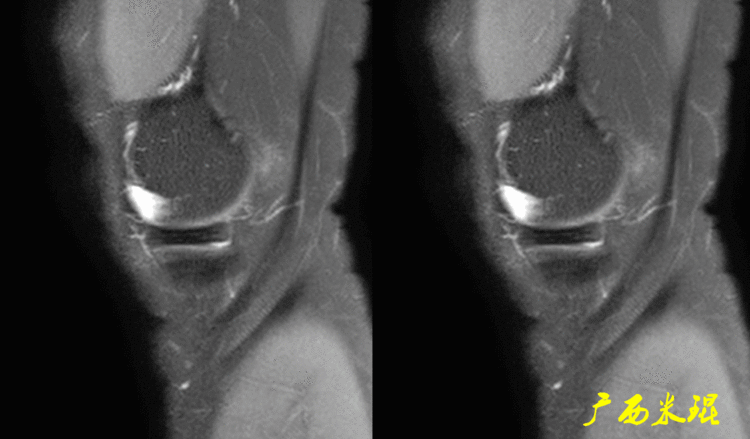

14、手术后半月板半月板手术后导致的半月板形态和信号的改变千变万化,有时候其改变可能在MR上比手术前还差,这种MR上的改变不代表手术存在问题,所以已故的冯华教授生前就经常说手术后的半月板MR很难评价。

下面矢状位MR是外侧半月板后角部分切除手术后,片上我们发现半月板后角部分缺失,半月板信号正常(因为手术前半月板没有退变)。

下面矢状位MR是内侧半月板后角水平撕裂部分切除手术后,半月板后角部分缺失,信号仍然不正常(因为手术前半月板已经有退变),真正的情况是关节镜下半月板外观是正常的,MR上看见的高信号影是半月板退变的Ⅱ级信号所致,由于手术切除面达退变的层面,MR上容易误诊为Ⅲ级信号。

下面矢状位MR是内侧半月板后角纵形撕裂缝合手术后,半月板外观完整,无分离,缝合处小片状稍高信号,这个高信号几乎不可能消失(半月板损伤痕迹永远存在)。

内侧半月板后角纵形撕裂缝合手术后,半月板外观完整,无分离,缝合处的线状稍高信号一般情况下也永久存在。

如同下面这张MR,左侧图像为手术前的,右侧图像为手术后的,术后病人疼痛等症状仍然存在,复查MR见外侧半月板前角分层,半月板前角的处理是有一定难度的,有经验的医生会考虑可能是手术者对前角的处理不够熟悉,没有通过另外的办法处理半月板前角的水平裂,不过也只能是猜测而已。所以,对于半月板术后的评估,症状的消失比MR重要!